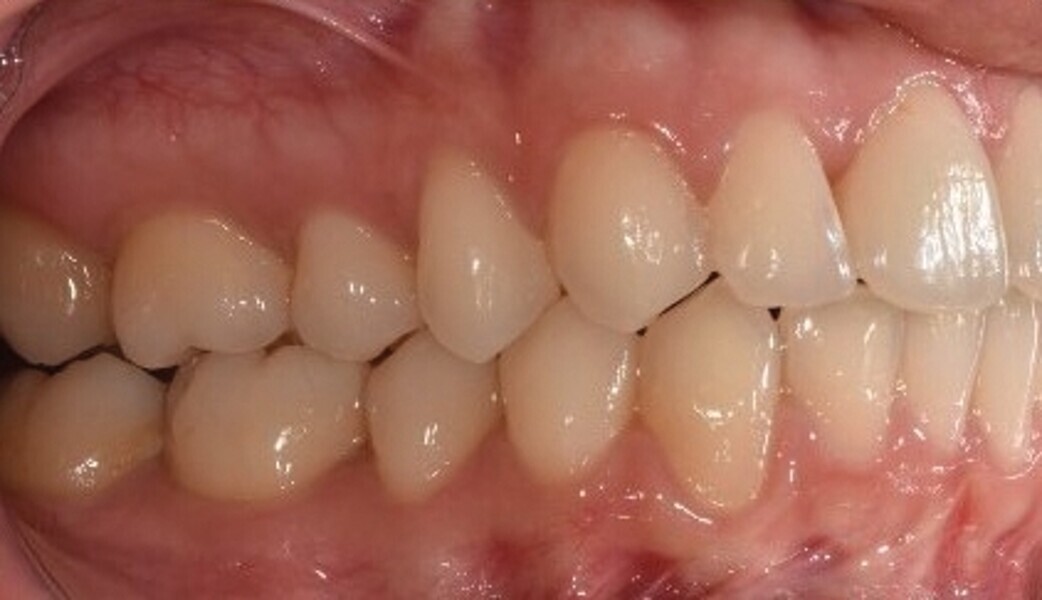

Après une période de onze mois et un nombre total de 66 aligneurs maxillaires et mandibulaires, le traitement est terminé et tous les objectifs sont atteints, à savoir une relation bilatérale de Classe I, une symétrie des arcades et la correction de l’encombrement (Fig. 6).

Fig. 6a : Photographie intraorale finale.

Fig. 6b : Photographie intraorale finale.

Fig. 6c : Photographie intraorale finale.

Fig. 6d : Photographie intraorale finale.

Fig. 6e : Photographie intraorale finale.